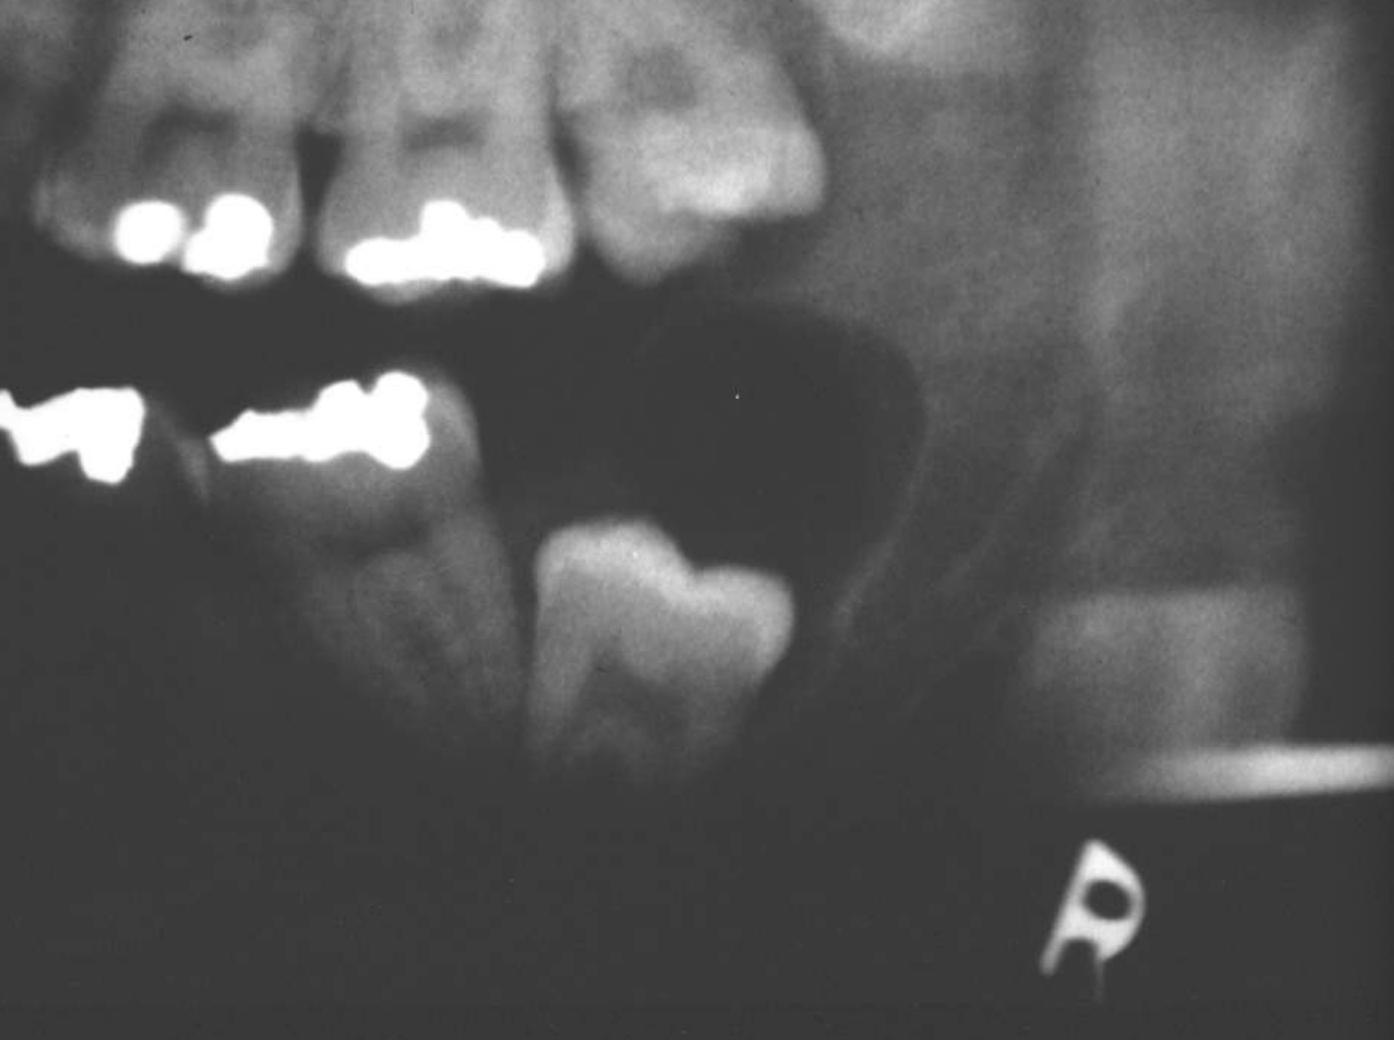

ameloblastoma

Multilocular

Root resorption

Thinning of inferior mandibular border